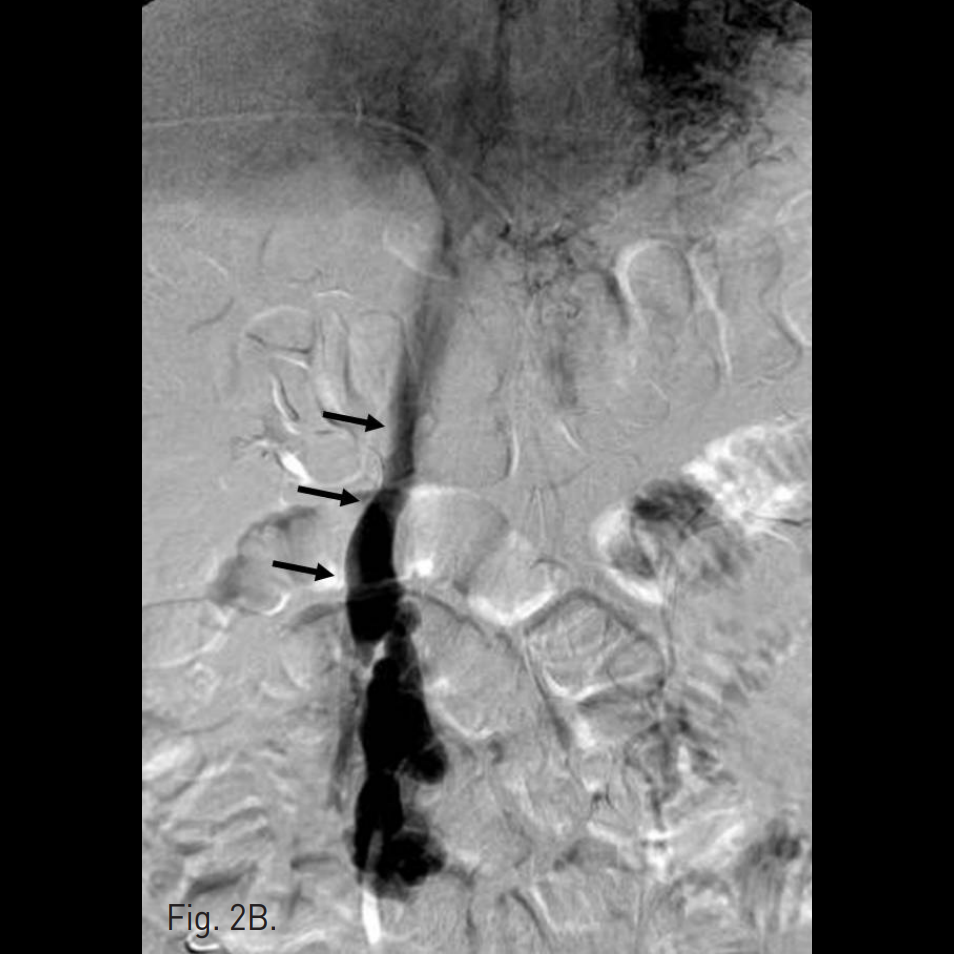

우후간문맥(right posterior portal vein)을 경피적으로 천자하여 6F sheath를 삽입하고 5F curved diagnostic cahteter를 상장간막정맥(superior mesenteric vein, SMV)에 위치시킨 뒤 시행한 direct portal venogram에서 주문맥(main portal vein)의 원위부에서 기시하는 비후된 혈관이 관찰되고 jejunal varix와 연결되어 있으며, 주문맥으로부터 다량의 혈류가 이 혈관으로 역류하고 있음(Fig. 2A). Varix의 nidus로부터 기시하는 drainage veins가 다수 관찰되고, 그 중 varix의 기시부에서 하대정맥으로 직접 유출되는 다량의 혈류가 있음(Fig. 2B).

Fig. 2

A. Direct portal venogram shows large amount of portal flow refluxed into hypertrophied vein (arrows) originated from distal portion of main portal vein, which supplies huge jejunal varix (arrowhead) without definitive con trast extravasation.

B. Multiple draining veins (arrows) from nidus of varix are found and one of them is hypertrophied and drained directly into IVC.